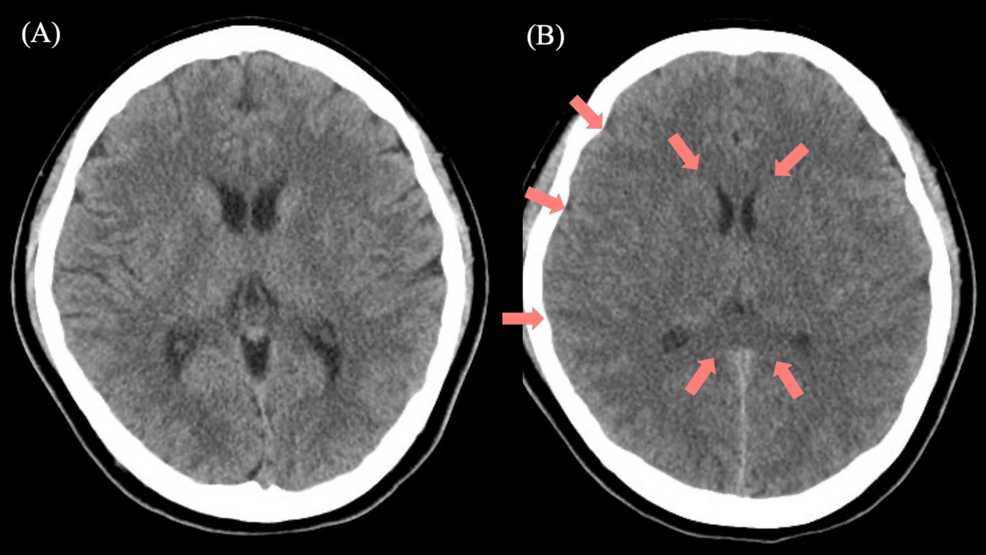

Un reporte de caso publicado por Cureus ha documentado un episodio de encefalopatía hiperamonémica grave derivado de una sobredosis de valproato de sodio de liberación prolongada.

De acuerdo con la literatura médica, la encefalopatía inducida por el ácido valproico puede ocurrir incluso en personas con una función hepática normal y, en ocasiones, a pesar de mantener dosis y niveles séricos normales del fármaco. No obstante, el caso reportado en Cureus se vincula específicamente a una sobredosis de la presentación de liberación prolongada.